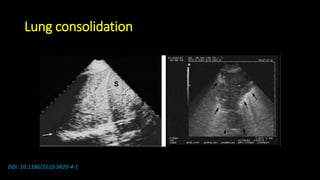

Lung consolidation

DOI: 10.1186/2110-5820-4-1